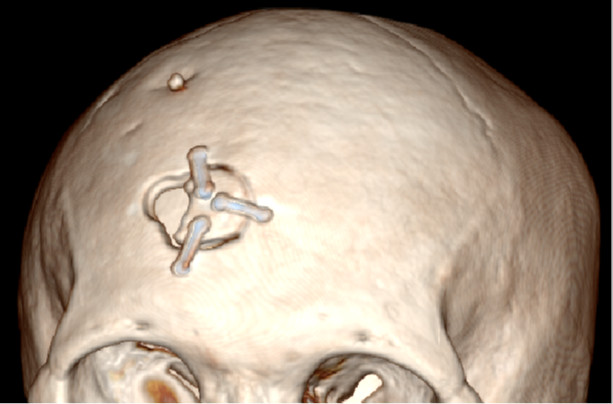

张军医师:3D打印导航内镜下血肿清除术视频1

张军医师:3D打印导航内镜下血肿清除术视频2